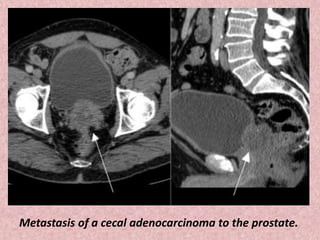

Metastasis of a cecal adenocarcinoma to the prostate.

Metastasis of acecal adenocarcinoma to the prostate.